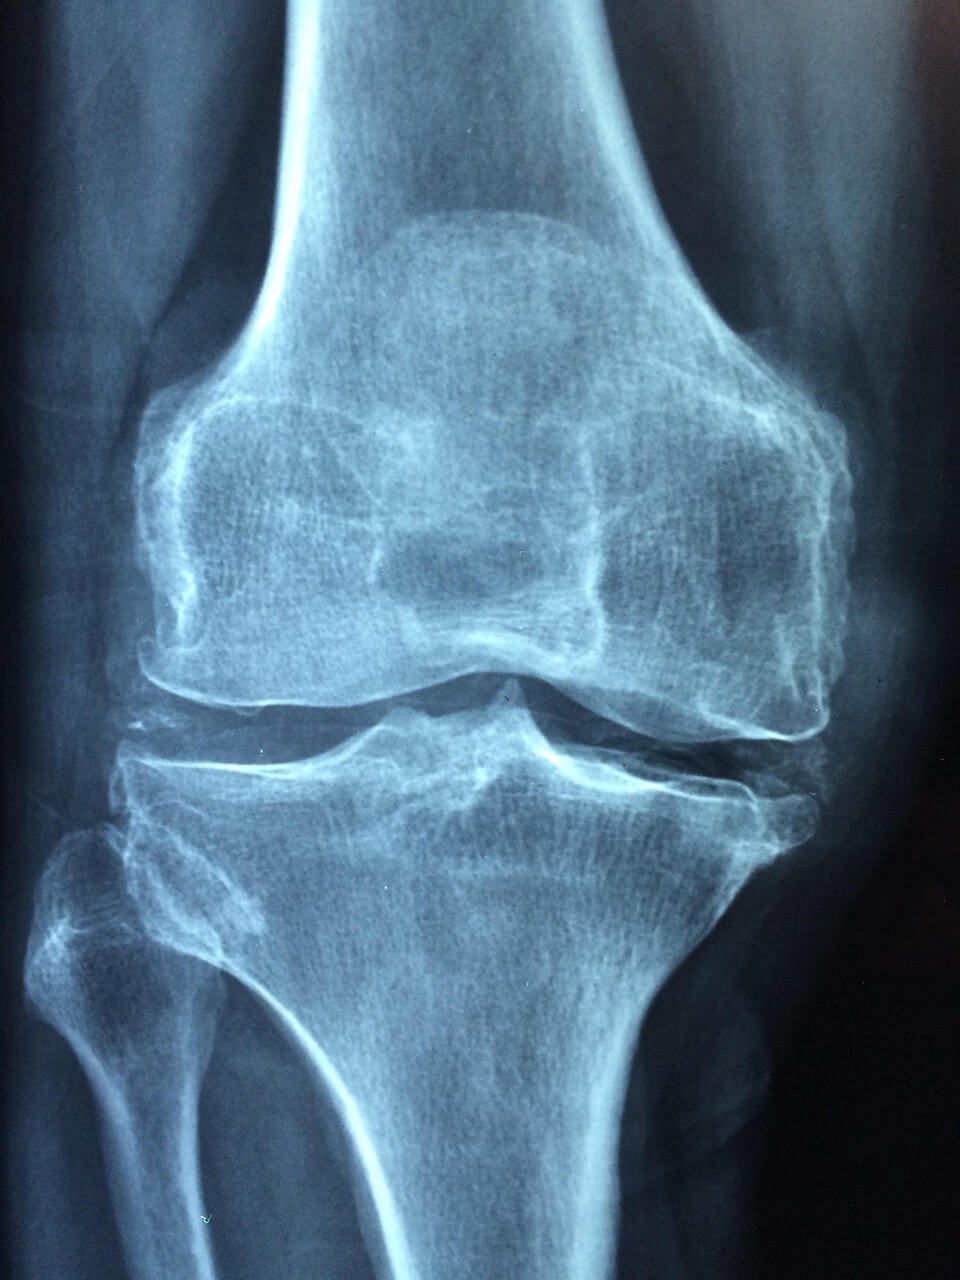

진단 방법

조기 진단을 위해 다음과 같은 검사가 필요합니다:

- X-ray: 뼈의 구조적 변형을 확인할 수 있으나 초기 단계에서는 잘 안 보일 수 있음.

- MRI: 가장 민감한 검사로 초기 골괴사를 정확히 확인 가능.

- CT 스캔: 병변의 위치와 범위를 더 정밀하게 분석 가능.

Q7. 골괴사는 어떤 검사로 확인하나요?

X-ray로 확인이 어려운 초기 골괴사는 MRI 검사가 가장 정확합니다. CT, 혈액검사도 보조적으로 시행됩니다.